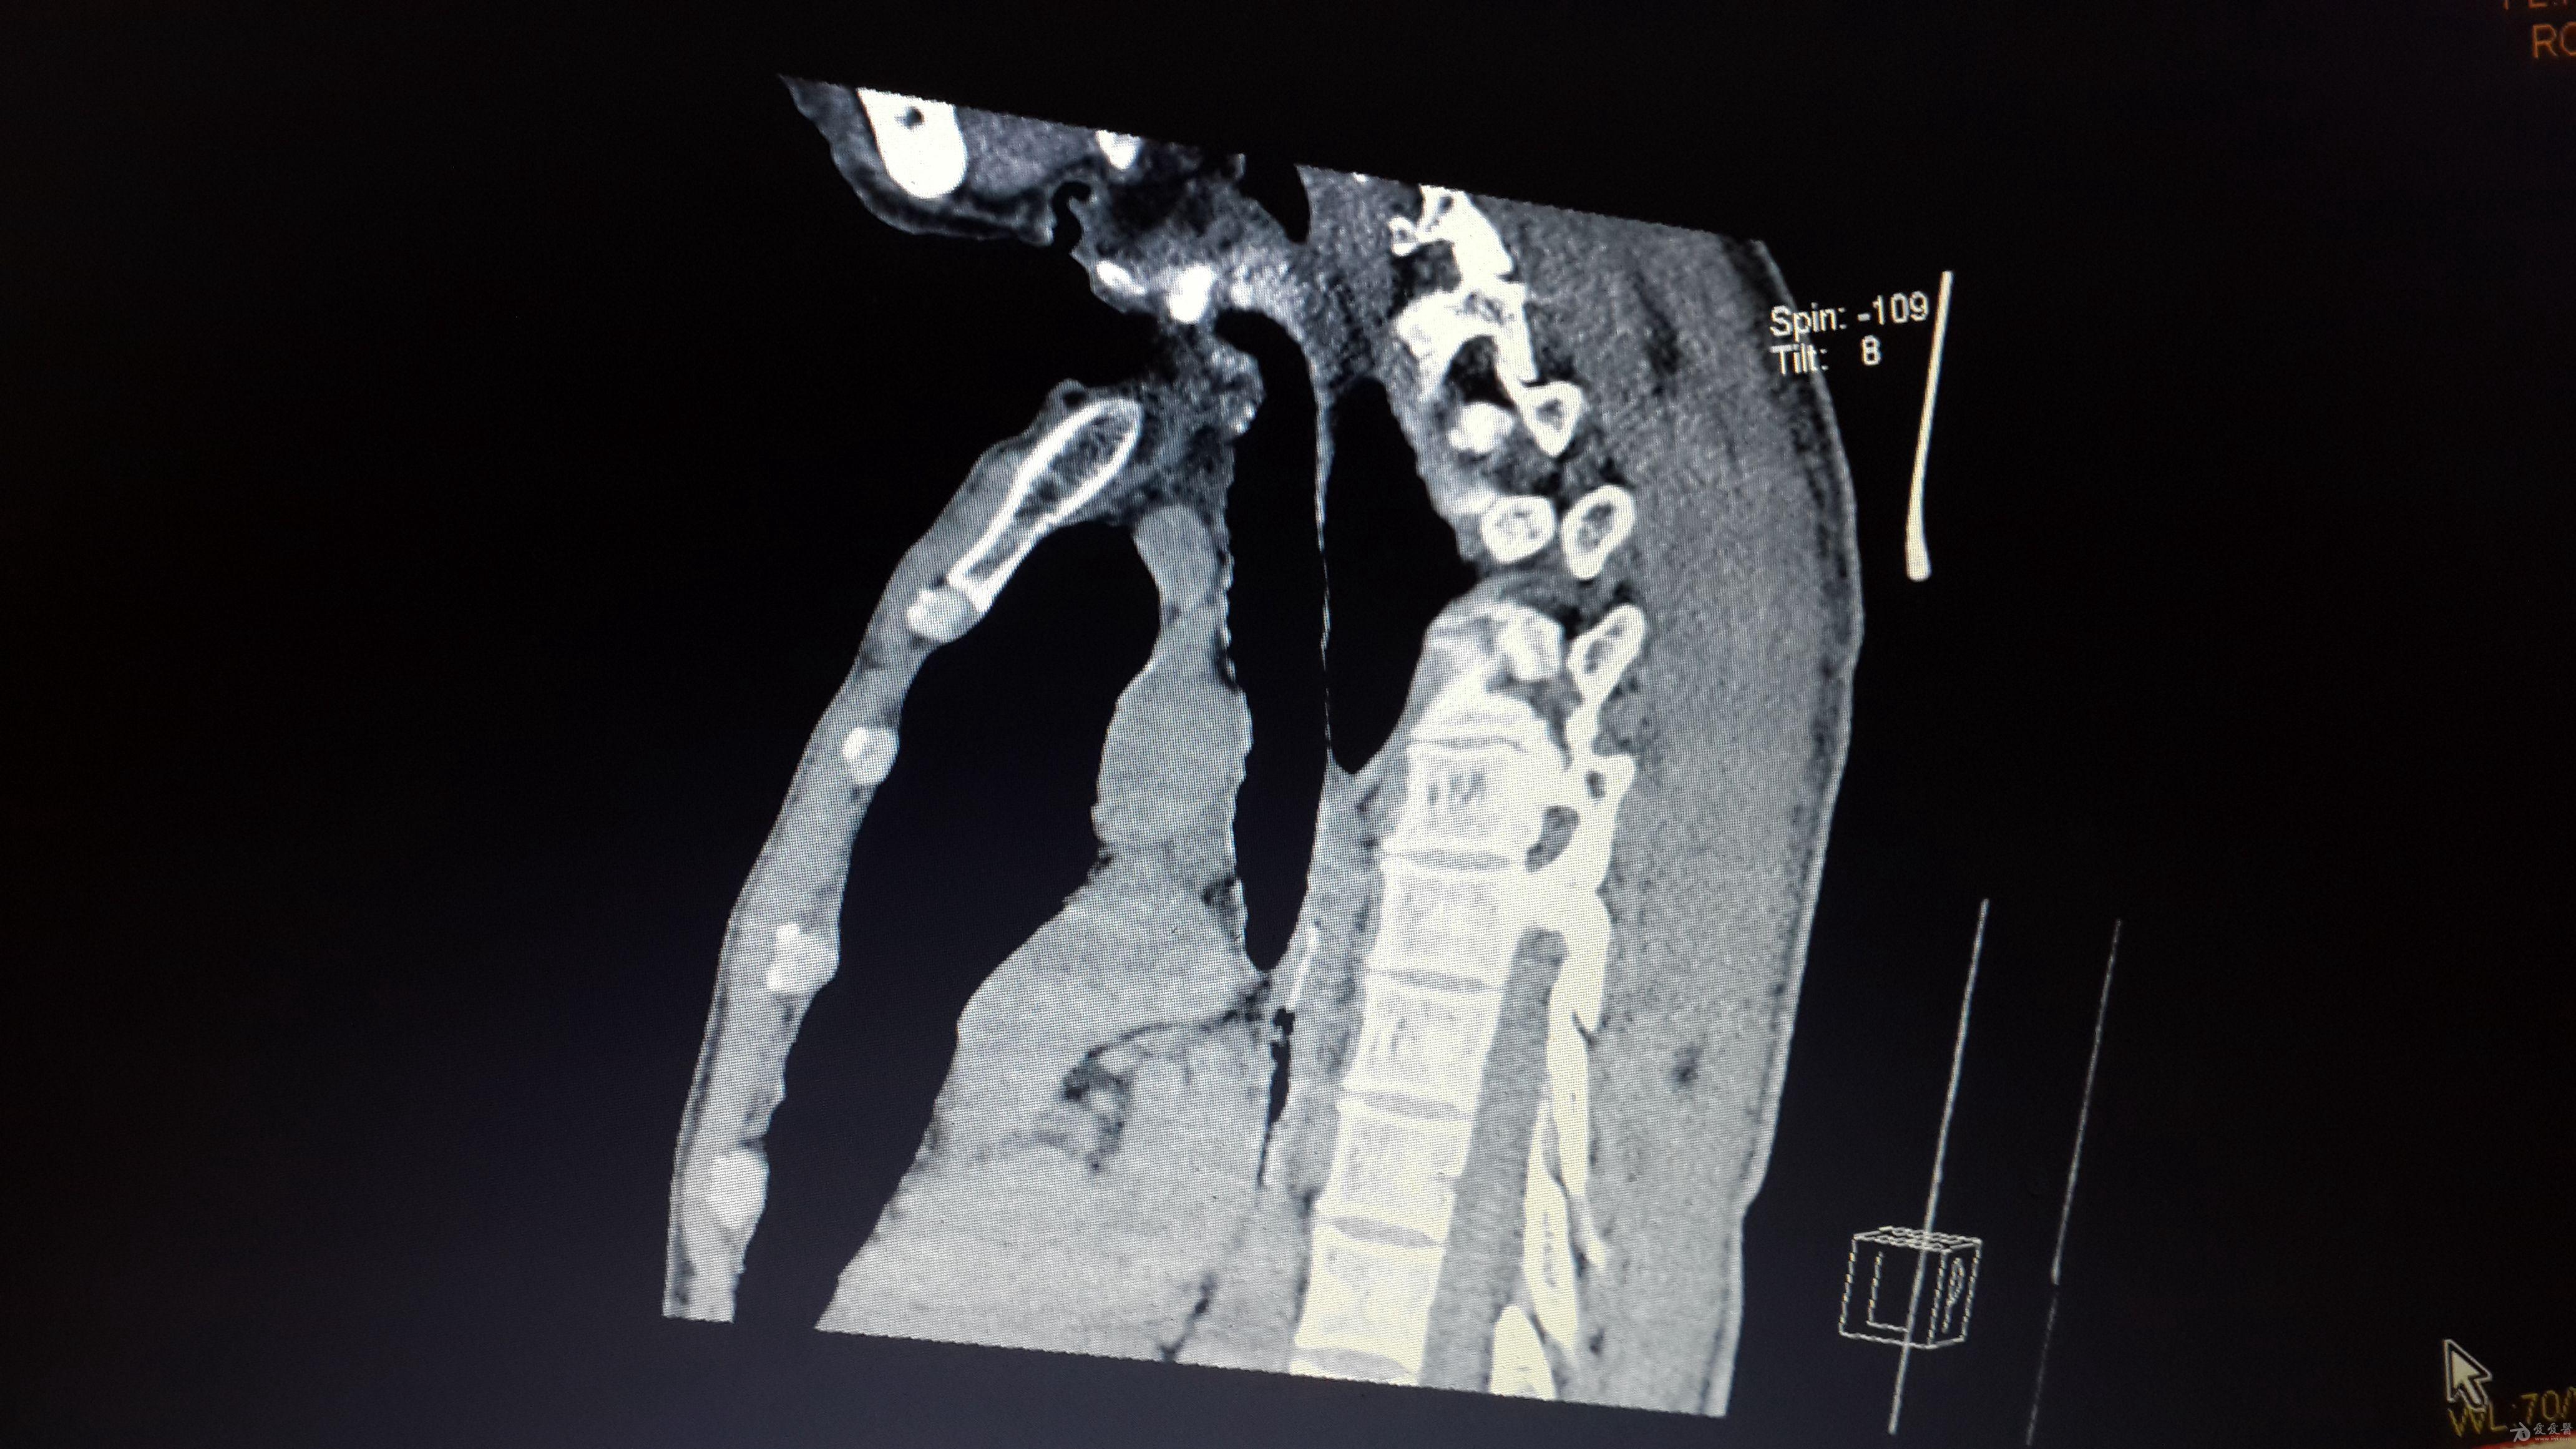

稍复杂的食道异物

图片尺寸4128x2322